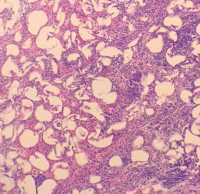

A 61-year-old female presented with abdominal pain, nausea, and vomiting. A CT scan with contrast was remarkable for a 12.5 x 8.0 x 8.5 cm right adrenal mass for which she subsequently underwent a right adrenalectomy. Histopathology of the tumor demonstrated encapsulated, well-circumscribed, proliferated adipose tissue with mixed hemopoietic elements consistent with myelolipoma weighing 190 grams.